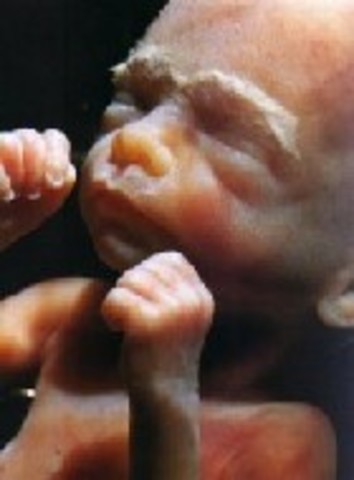

• Week 10

Week 10

Embryo becomes a fetus the size of a strawberry. The neck begins to take shape, body muscles are almost done developing, baby begins moving, fingerprints are formed, nipples and hair follicles begin to form.